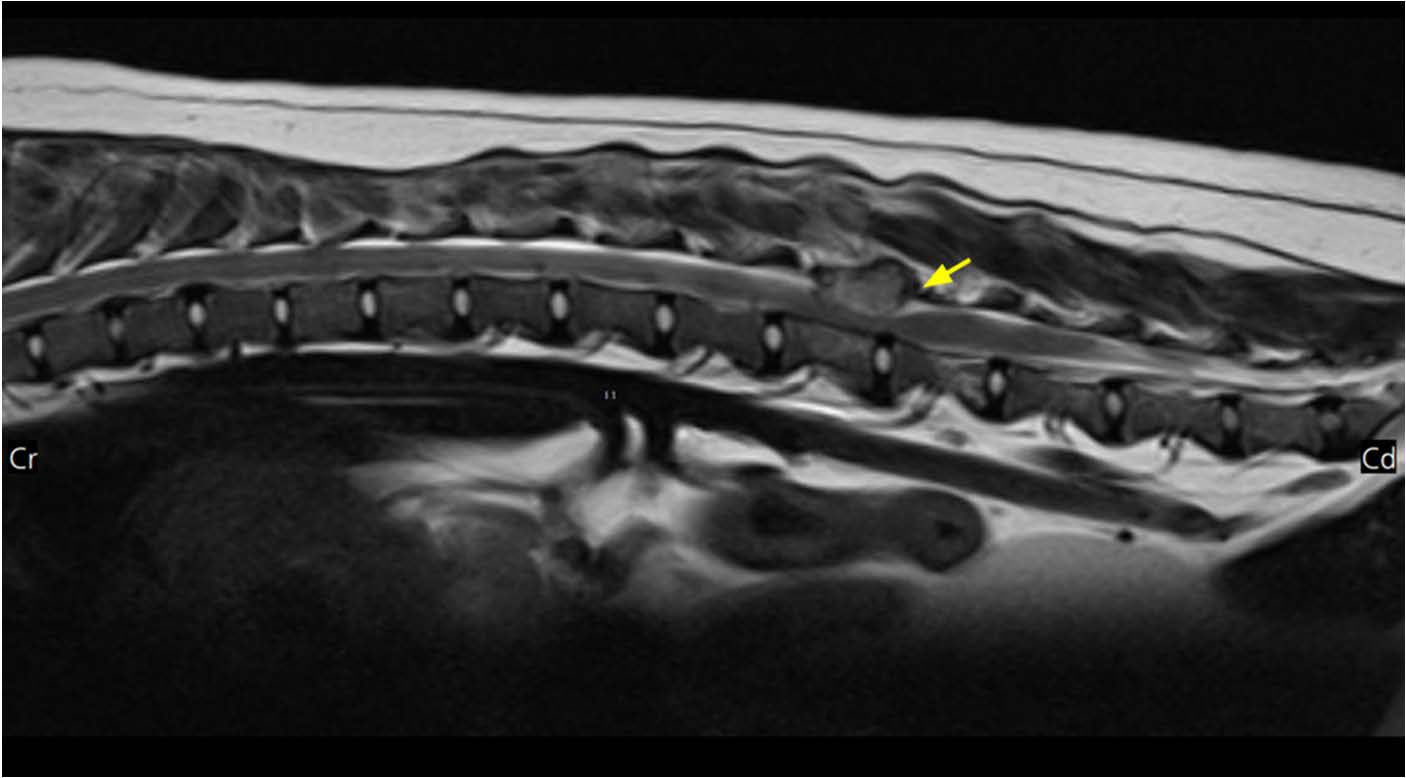

对脾脏、肝脏和外周淋巴结进行了细针穿刺抽吸。脾脏和肝脏的细胞学分析显示存在大量浆细胞,其特征为圆形细胞核、嗜碱性细胞质和明显的核周透明区(下图)。外周淋巴结中未观察到显著的肿瘤细胞。

↑ 脾脏(A)和肝脏(B)的细胞学检查。主要观察到圆形细胞,具有蓝色细胞质、圆形细胞核和核周透明区。

根据影像学和细胞学检查结果,初步诊断为多发性骨髓瘤,累及椎体、髂骨、耻骨、肋骨及腹部器官(肝脏、脾脏和胸腹腔淋巴结)。由于患者临床状况较差,未进行组织病理学检查和骨髓活检。